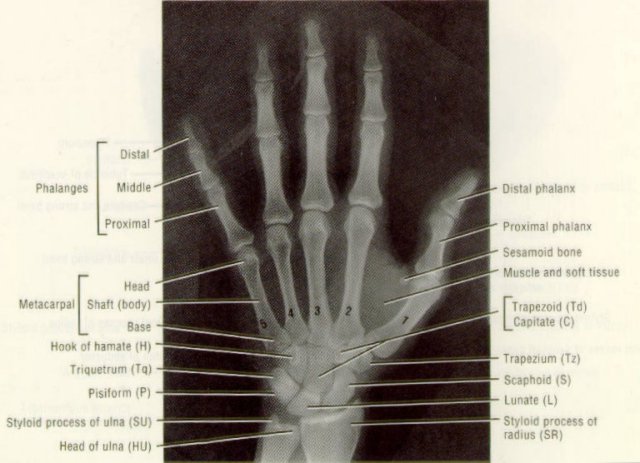

This picture shows the relation of the trapezium to the thumb metacarpal and the normal positions of the thumb phalanges, also called phalanxes.